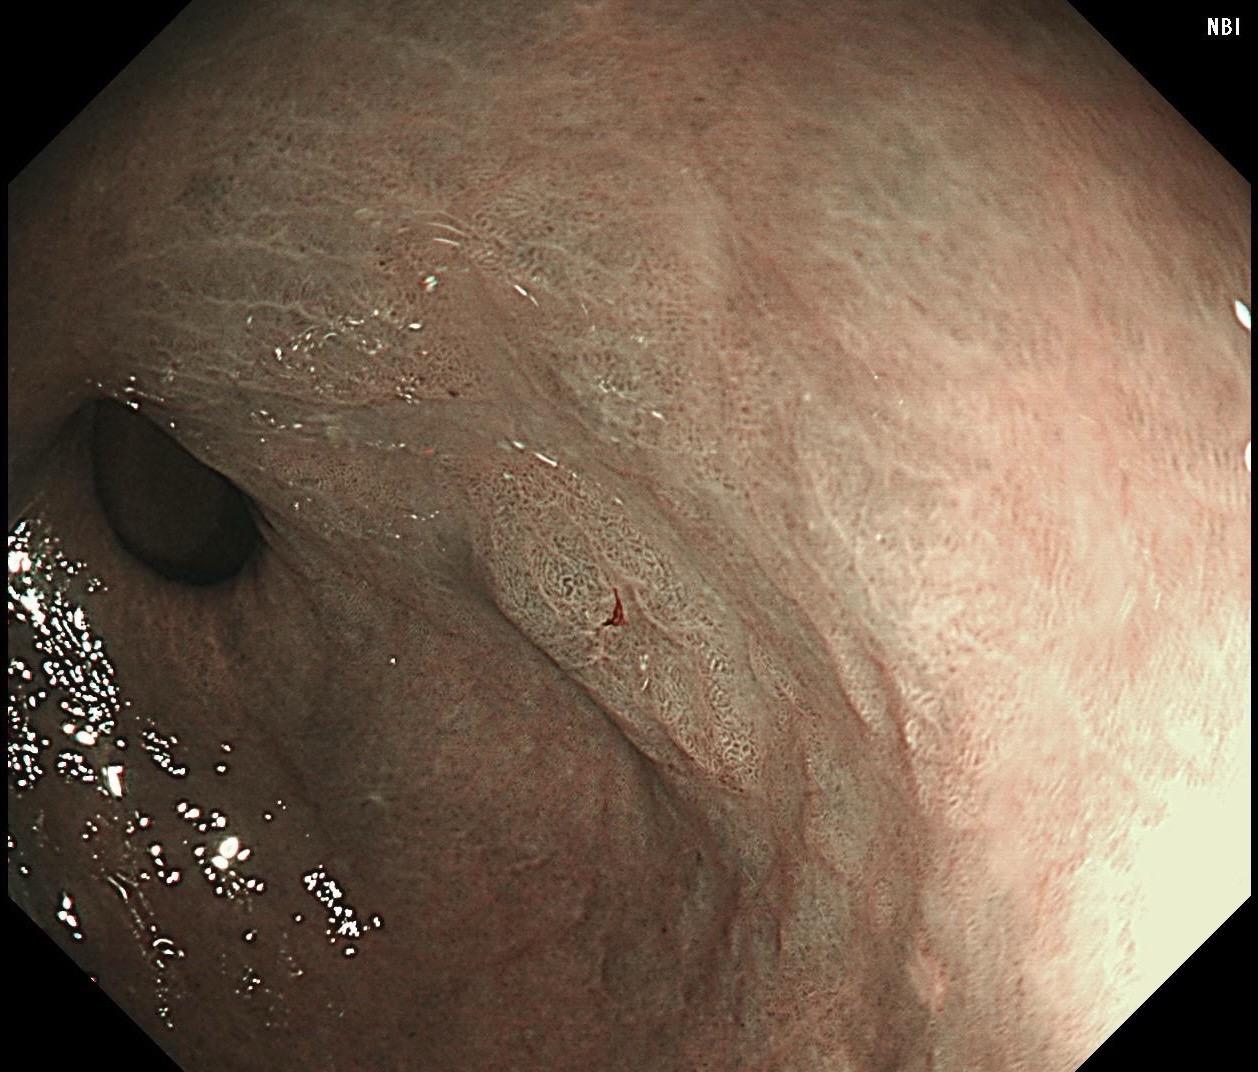

萎缩背景,注意那些微小的发黄色调。